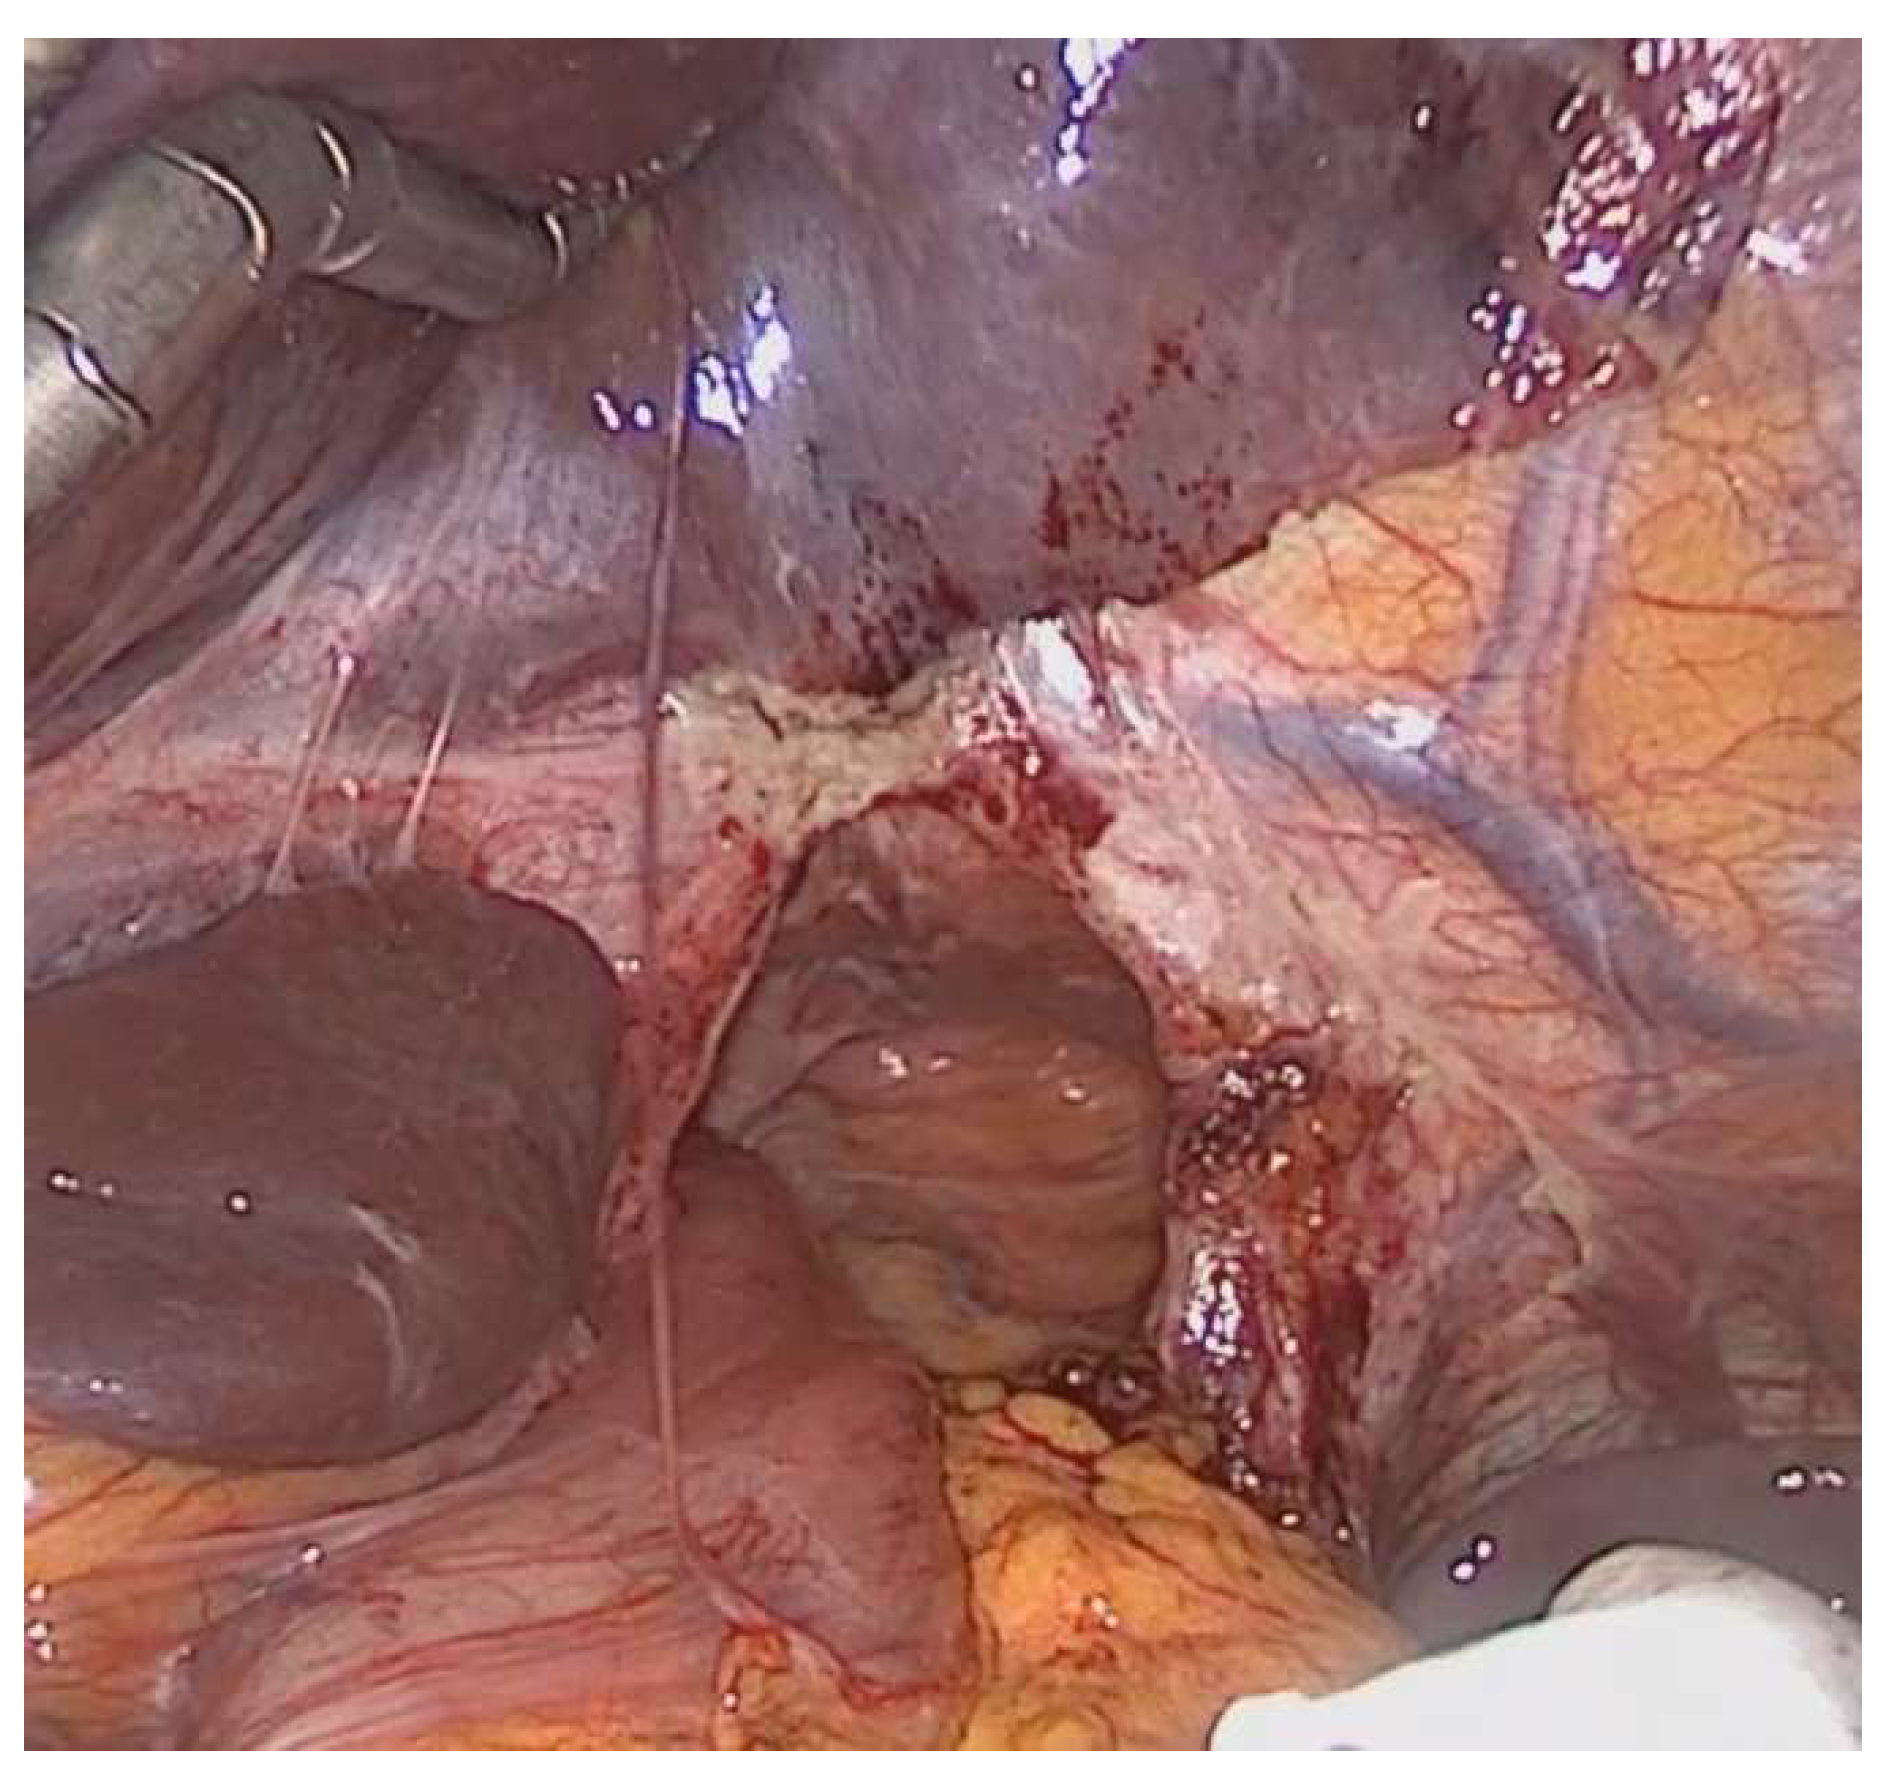

| Surgical repair, n (%) | |

| Laparoscopic | 16 (84.2) |

| Conversion | 2 (12.5) |

| Open | 3 (15.8) |

| Gastropexy | 8 (42) |

| Hiatoplasty | 9 (47.4) |

| Mesh augmentation | 4 (21) |

| Colopexy | 15 (78.9) |

| Recurrence rate, n (%) | 6 (31.6) |